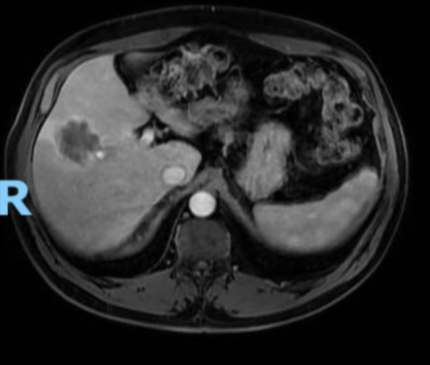

A ressonância magnética tem maior sensibilidade para metástases pequenas, enquanto a tomografia computadorizada é essencial para estadiamento. O PET-CT auxilia na identificação de doença extra-hepática, e a ultrassonografia intraoperatória detecta lesões ocultas.